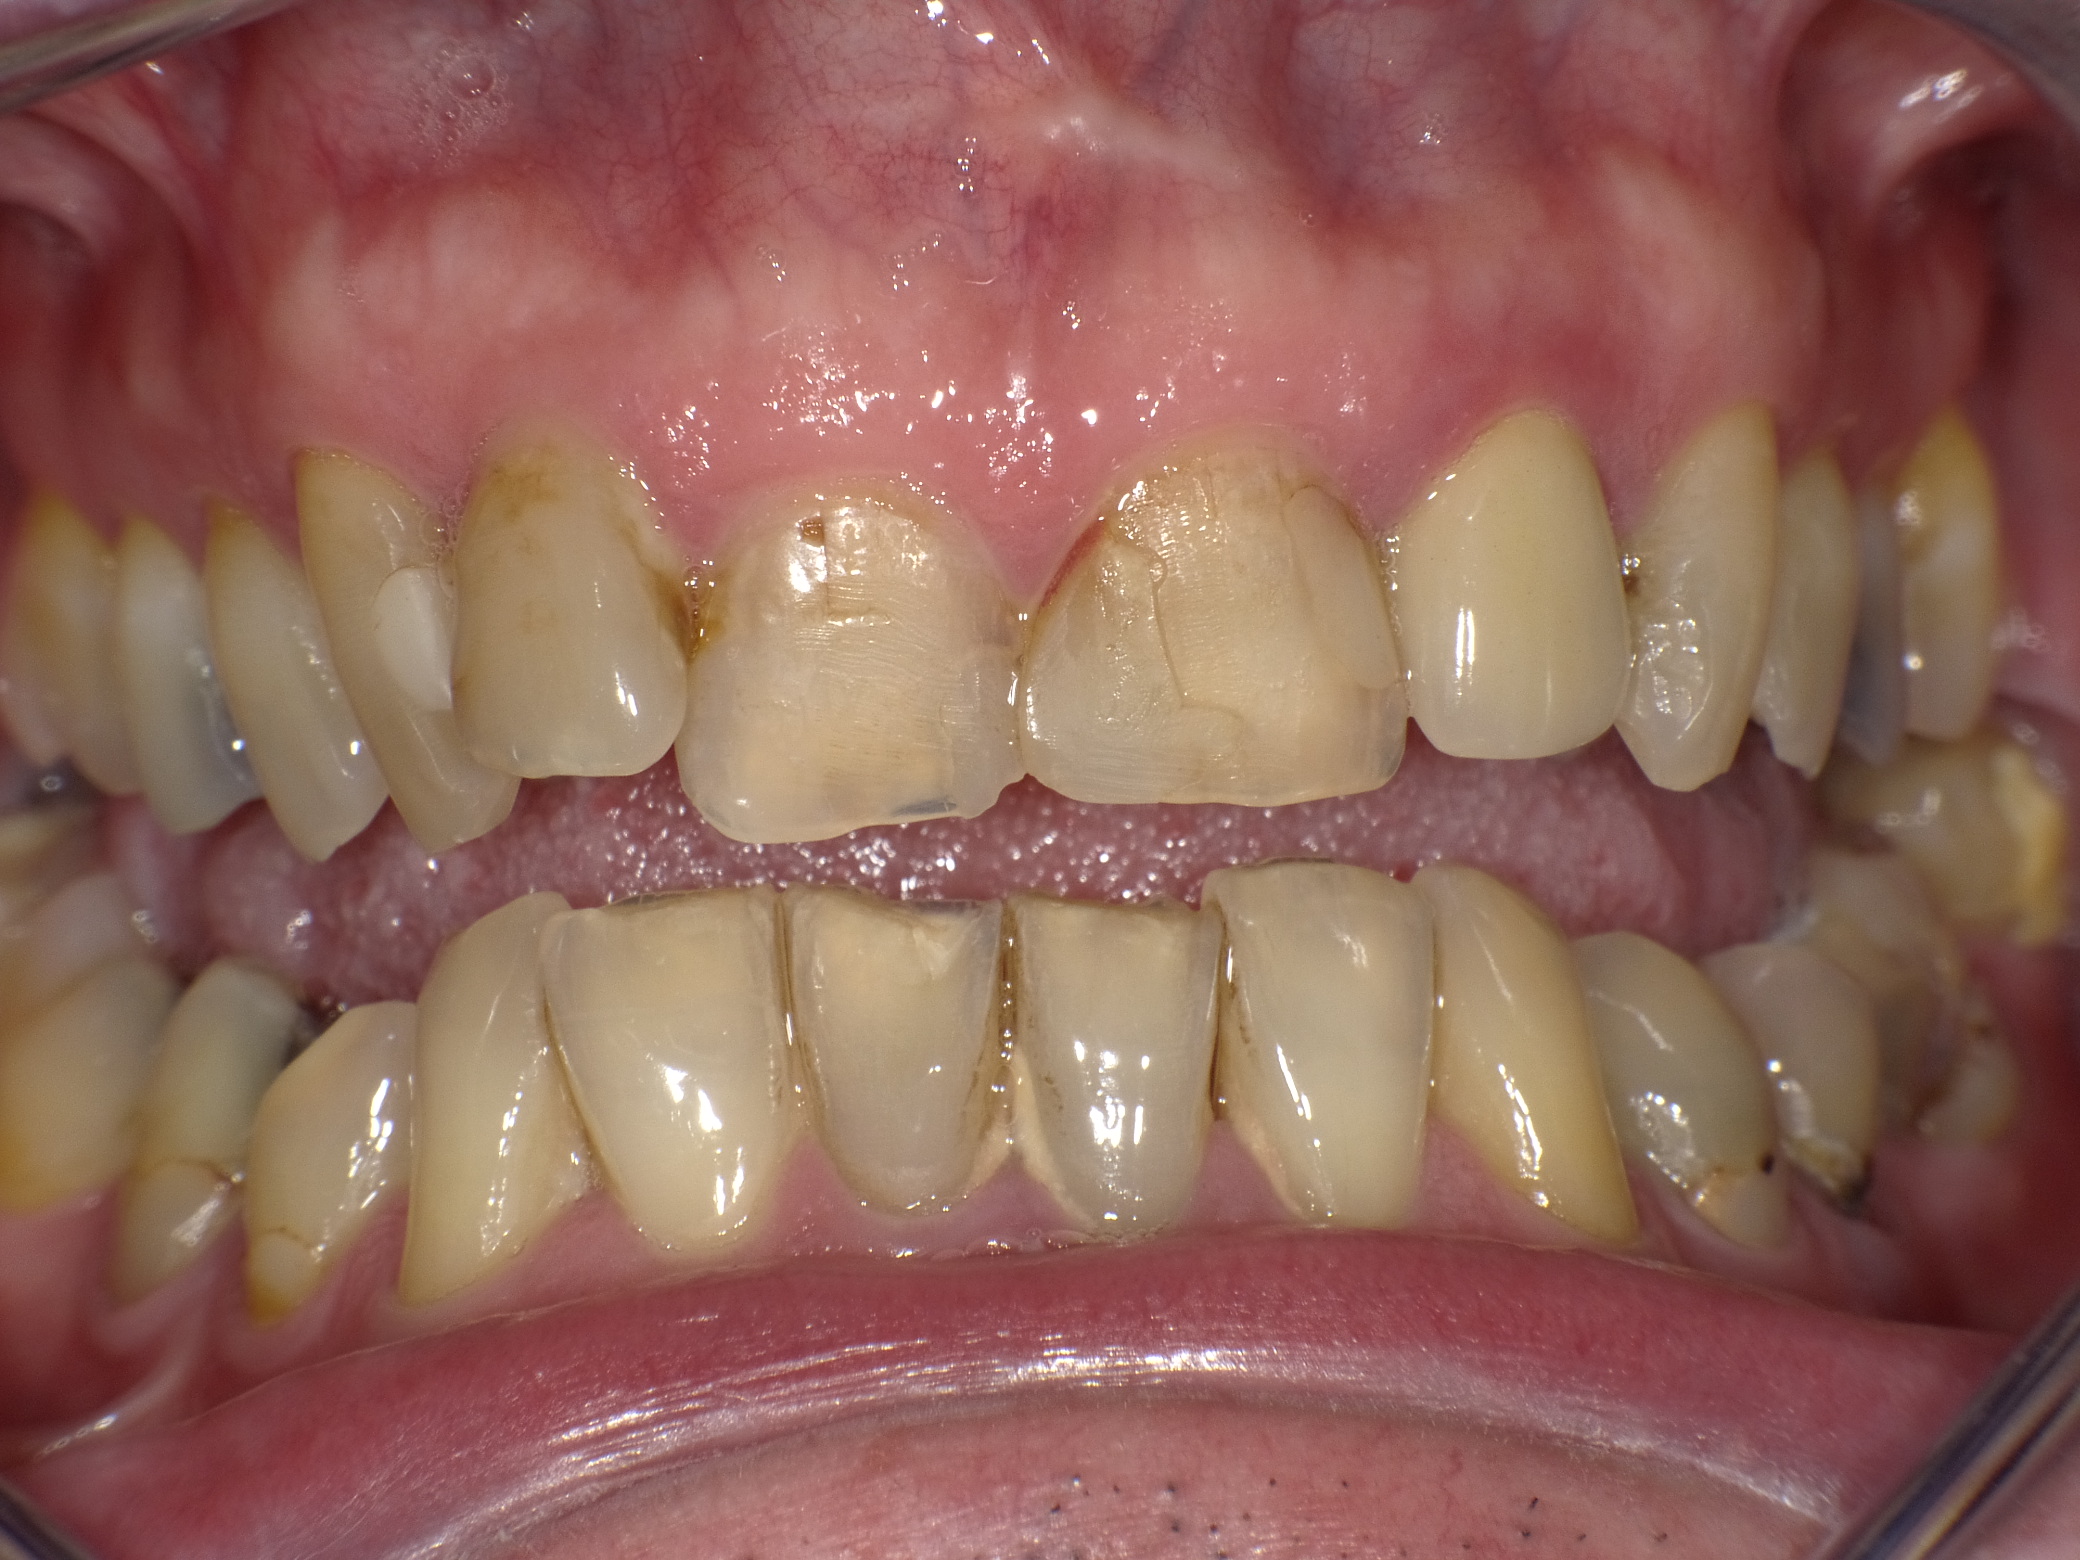

Diverse Vorbehandlungen mit für die Patientin absolut inakzeptablem Ergebnis

Vorher: Diverse Vorbehandlungen mit für die Patientin absolut inakzeptablem Ergebnis

Komplette Veränderung mit vollkeramischen Kronen und Veneers in nur 2 Langzeitterminen; auch hier nachher ganz anderes Auftreten der Patientin, die ihre Zähne jetzt gerne zeigt und wieder gerne lacht

Nachher: Komplette Veränderung mit vollkeramischen Kronen und Veneers in nur 2 Langzeitterminen; auch hier nachher ganz anderes Auftreten der Patientin, die ihre Zähne jetzt gerne zeigt und wieder gerne lacht